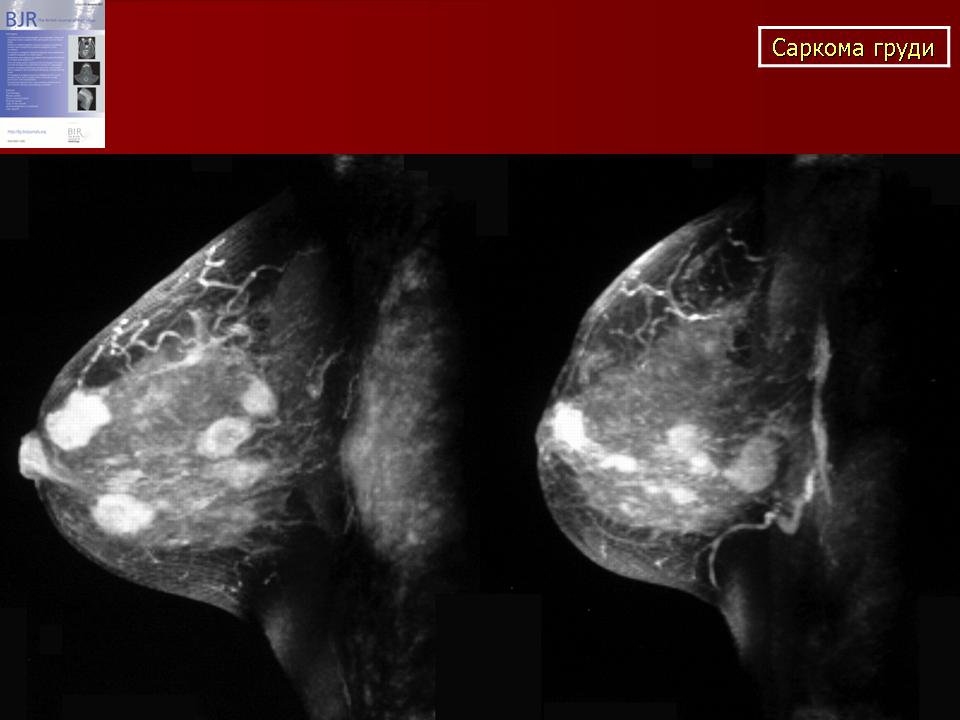

Врожденные аномалии молочной железы

Синдром Поланда представляет собой сочетание деформации грудной клетки и отсутствия или гипоплазии грудных мышц и молочной железы, связанное с укорочением и брахисиндактилией верхней конечности. Клиническая картина широко варьируется; следовательно, реконструктивные процедуры должны быть адаптированы к деформации, начиная от стабилизации или увеличения грудной стенки, динамического переноса мышц, изменения положения соска и ареолы и увеличения груди с использованием протеза или переноса аутологичной ткани. Другие врожденные аномалии молочной железы включают избыточные соски и ареолы (полителия) и груди (полимастия), которые обычно можно обнаружить на эмбриональном грудном гребне. Отсутствие соска, ареолы (ателии) или ткани молочной железы (амастия) встречается реже.

Другие врожденные аномалии молочной железы включают избыточные соски и ареолы (полителия) и груди (полимастия), которые обычно можно обнаружить на эмбриональном грудном гребне. Отсутствие соска, ареолы (ателии) или ткани молочной железы (амастия) встречается реже.

Ключевые слова: Синдром Поланда, молочная железа, грудная мышца, полителия, полимастия, ателия, амастия